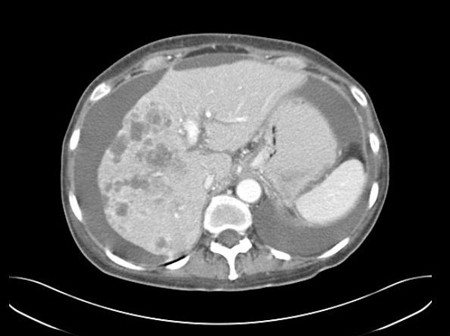

• CT chest/abdomen/pelvis